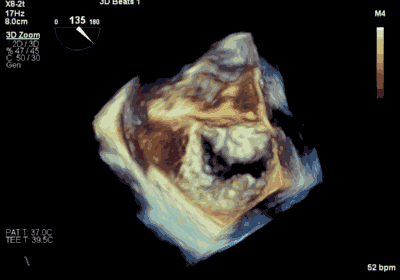

▲ 术前超声检查显示重度二尖瓣反流

▲ 术后超声检查显示轻度二尖瓣反流

患者为73岁老年男性,既往合并冠心病、持续性心房颤动、肾功能不全病史,此次主诉“反复胸闷气促3月余”入院。诊断:心脏瓣膜病 二尖瓣脱垂伴重度关闭不全 心功能Ⅲ级(NYHA分级)。术前经胸超声心动图示:左房扩大,二尖瓣前后叶冗长、P2脱垂合并重度反流(Type II类 DMR/MR4+)。心脏测值:LA 54 x 58mm,LVD 60mm,EF% 60%,PASP 36mmHg。经食管超声心动图示:二尖瓣环左右径38mm,反流束缩流颈宽度为8.5mm,EROA 0.72cm2(PISA),舒张期二尖瓣口平均跨瓣压差2mmHg。

王焱、王斌教授团队通过术前和台北荣民总医院(Taipei Veterans General Hospital)宋思贤教授进行了详细的讨论并制定了最优的手术策略,同时术中视频连线获得宋思贤教授的技术支持,华体会体育官方网站 超声内科苏茂龙教授负责术中超声心动图引导。患者全麻以后,在经食道超声心动图和X射线引导下,经股静脉入路,将MitraClip瓣膜夹顺利送至二尖瓣前后叶交界中心处,成功捕捉二尖瓣前叶A2和后叶P2,经超声心动图反复确认瓣叶夹持牢固后,测定有效夹持长度11mm,评估反流量降至微量,释放瓣膜夹,超声心动图评估瓣膜夹位置和功能良好,测定左房压降至11/6mmHg,再次评估反流量仍为微量,手术顺利完成。